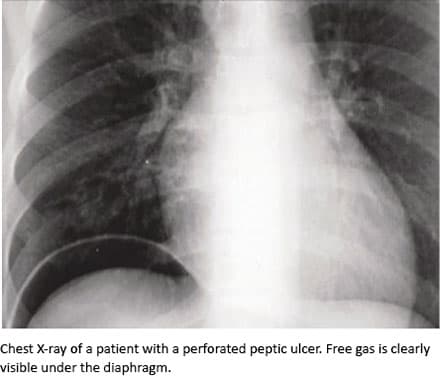

Perforated peptic ulcer (PPU) is a surgical emergency with mortality rates reaching 25-30% [1]. Perforation of the gastro-intestinal wall by erosion from a peptic ulcer leads to acute peritonitis, and sepsis is believed to account for 40-50% of fatalities [1, 2]. Reoperation following surgery for PPU is associated with adverse outcome [3, 4]. Timely and adequate identification of PPU patients at increased risk of reoperative surgery and adverse outcome is important, as this will enable a thorough and adequate planning of the pre-, intra-, and post-operative phases [4, 5].